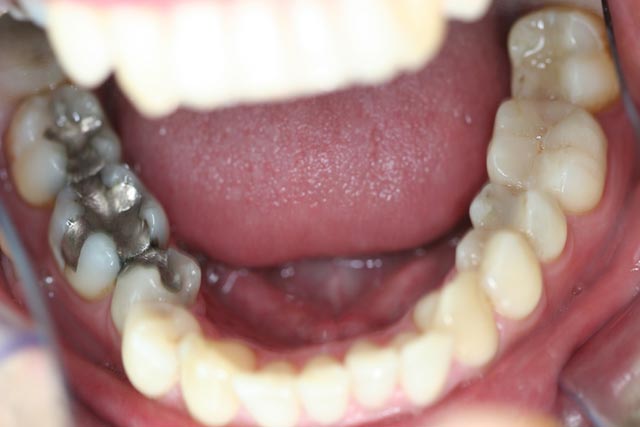

El relleno de amalgama gris-metálico se elabora mezclando mercurio líquido (porción del 50%) con un polvo de aleación.

Siete empastes de amalgama corresponden a un peso de unos dos gramos de mercurio puro. En los países accidentales la media son doce empastes por ciudadano (3 a 4 gramos). Tan solo un gramo de mercurio conduciría a la muerte por inyección directa. Soportamos esta gran cantidad de mercurio porque en primer lugar en su forma metálica, que relativamente es poco tóxica y en segundo lugar porque se disuelve y es absorbido por el cuerpo lentamente. A solo 20 grados centígrados se evapora el mercurio y en esta forma de vapor es altamente tóxico. Al existir en la boca a veces a temperaturas entre 40 y 60 grados, continuamente se libera vapor de mercurio y es absorbido por el organismo. Esta liberación de mercurio aumenta al masticar fuertemente, pasta dentífricas con fluor, comidas y bebidas calientes o ácidas, fumar y masticar chicles.